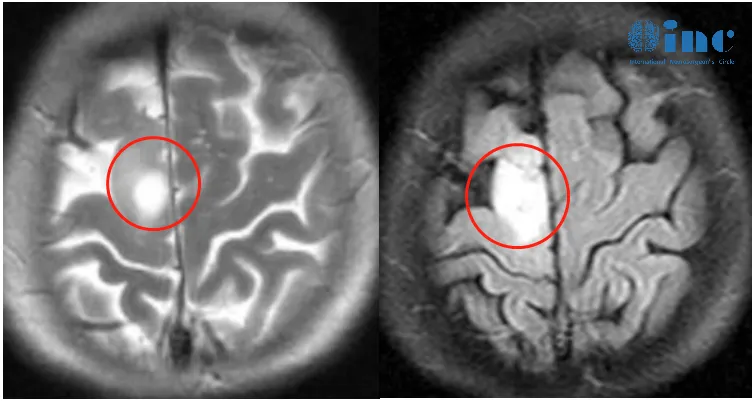

▼患者术前情况:2023年1月底罗女士突然左腿失去知觉摔倒,后面又类似情况发生几次。3月份,他们来到当地医院进行检查,颅脑MR+增强显示:右侧额叶异常信号灶,考虑低级别胶质瘤。当地医生建议:目前肿瘤比较小,手术怕伤到运动神经,也怕切不干净,先保守治疗,等腿和手的功能都出现障碍了,为了保命延长生存期不得已时再做手术。此时正恰逢巴教授中国行期间,他们便立马通过INC紧急整理资料咨询巴教授。

▼治疗过程:4月2日,罗女士和家人一致决定找巴教授手术,这时距离罗女士咨询巴教授仅过去了2天。

最终,INC德国巴特朗菲教授为额叶胶质瘤合并癫痫发作患者——66岁的罗女士顺利行肿瘤切除,在术中导航、术中核磁、术中神经电生理监测下,肿瘤取出的同时也保护了大脑正常功能。